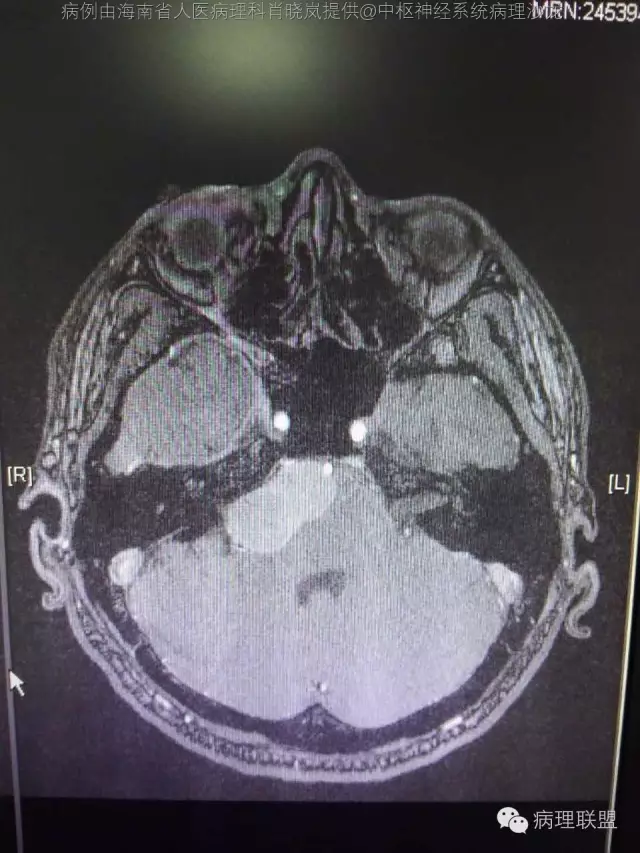

男,36岁。右面部麻木1月余。手术所见:右CPA区见5Ⅹ4cm肿块,灰褐色,血供丰富,质韧,界清。临床诊断:右侧桥小脑角区占位:脑膜瘤。大体检查:灰黑色碎组织一堆,大小2.5Ⅹ2.5x0.5cm,免疫S100,HMB45阳性。Ki67指数低。(病例由海南省人医病理科肖晓岚提供,致谢!)

@海南省人医病理科肖晓岚 影像也是符合黑色素相关肿瘤,可请影像专业的老师分析一下CT结合MR对产生黑色素的病变还是具有一定的特征性的,本例黑色素含量似乎不太多,所以跟脑膜瘤差不太多了,需要请影像老师分析!